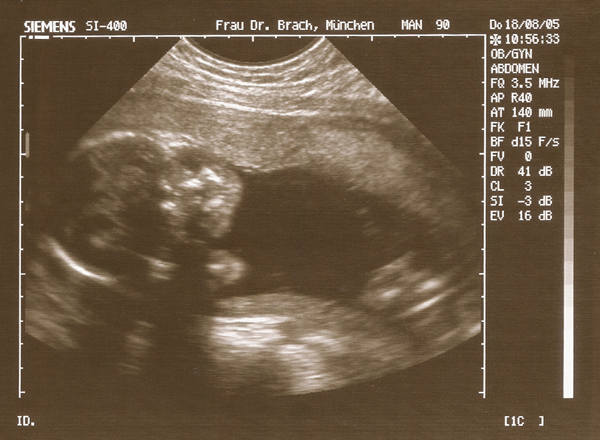

18.08.05 - 24. Woche - 27,2cm